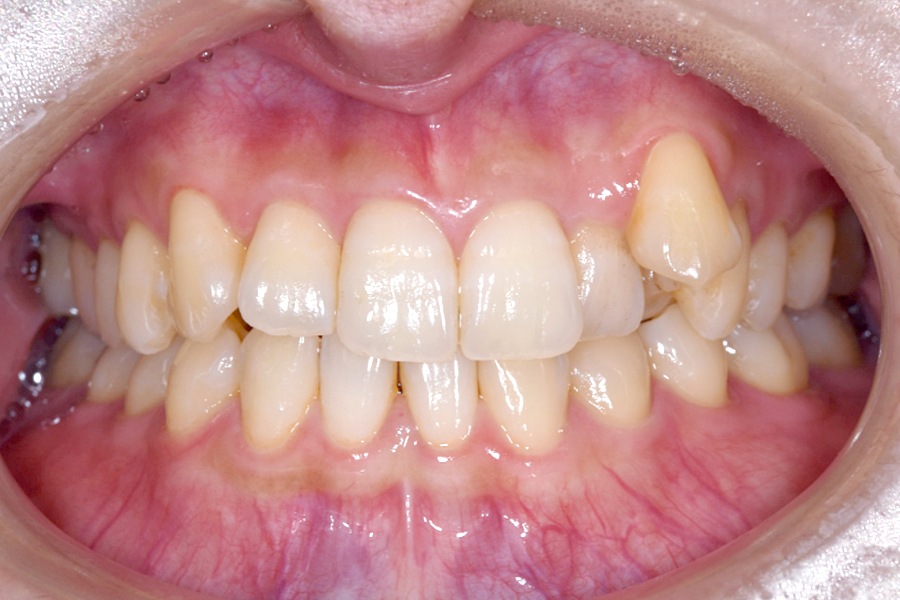

| 主訴 | 歯並びを治したい |

|---|---|

| 治療期間 | 1年9か月 |

| 治療費 | ¥1,023,800(税込) |

| 治療内容 | 目立ちにくいマウスピース矯正(非抜歯矯正) 歯と歯の間に隙間をつくることにより、 歯列弓を広げながら治療を行いました。 |

| 治療のリスク | ・後戻りする可能性があるので リテーナーを最低でも矯正期間以上はつけること ・歯の移動中に、歯の神経が過敏になり冷たいものや熱いものがしみたりする場合があります。 |